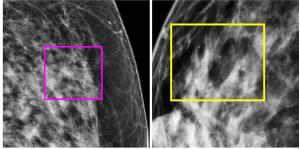

Employing a 77-second scan time for obtaining ultrafast breast MRI views, researchers found a 92.1 percent AUC for differentiating between benign and malignant lesions, according to new prospective study.